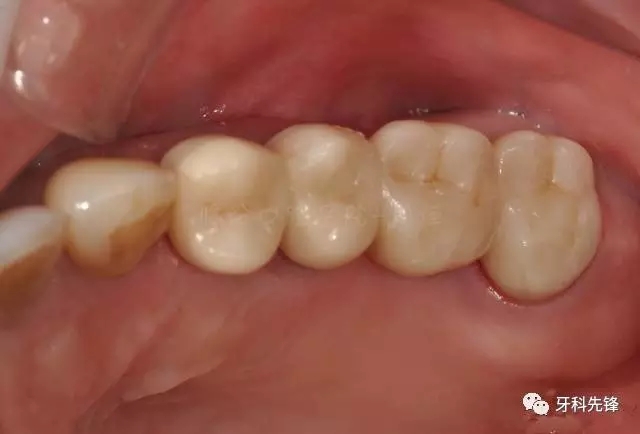

圖22烤瓷冠咬頜照

640.webp (26).jpg

圖29術(shù)后頰面照

640.webp (33).jpg